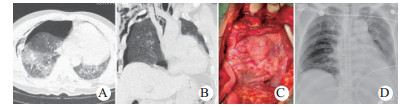

| 图 2 例4紧急剖胸心包减压、心脏修补,剖腹脾切除(A:术前CT示血心包; B、C:心包减压后钳闭左心耳破口; D:术后15 d超声心动图示二尖瓣重度反流; E:术后130 d超声心动图复查示二尖瓣轻度反流) Fig 2 Case 4 having emergency decompression of thoracic pericardium, cardiac repair, and abdominal splenectomy (A: Preoperative CT showed blood pericardium; B and C: Pericardial decompression performed to close the rupture of left auricle; D: Echocardiography showed severe mitral regurgitation on postoperative day 15; E: Echocardiography showed mild mitral regurgitation on postoperative day 130) |

| 图 3 例5伤后9 d心包疝嵌顿,松解和心脏复位术(A、B:术前CT示心包疝嵌顿和左移; C:术中见心肌挫伤后肉芽期; D:术后3 d胸部X线平片示心脏已复位) Fig 3 Case 5 showed incarceration of pericardial hernia, decompression and cardiac reduction on 9 days after injury(A and B: Preoperative CT showed incarceration and left shift of pericardial hernia; C: The granulation stage after myocardial contusion observed during the operation; D: The chest X-ray showed the restored heart on postoperative day 3) |